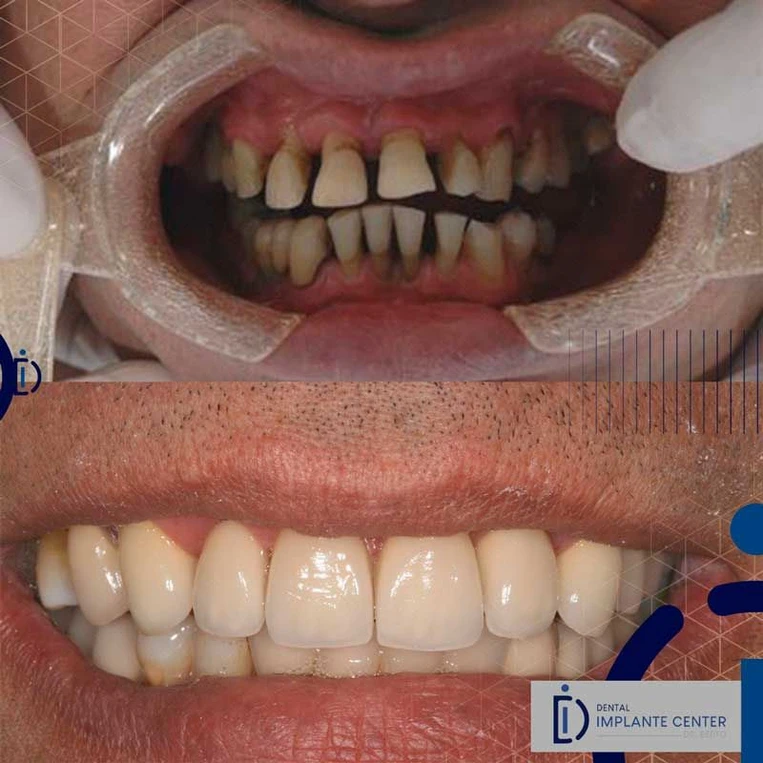

Solução para reabilitação de para quem perdeu todos os dentes da parte superior ou inferior. Composta por uma peça inteira e fixa que reestabelece a qualidade de vida dos pacientes

Técnica moderna que restabelece a função de mastigação e estética em poucos dias. Indicada para pacientes que perderam um dente, dois dentes ou todos os dentes.